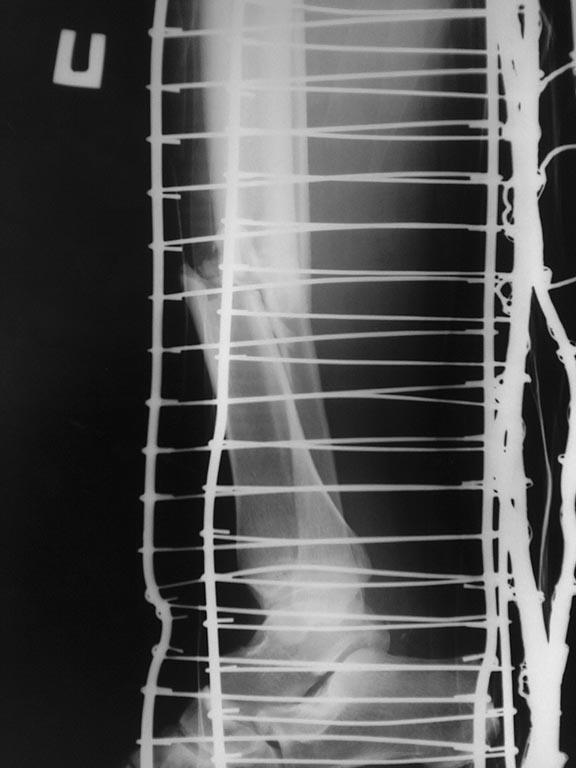

Обратилась на консультацию молодая девушка 1977 г.р. - получила травму в

июне 2012 - оперирована. Есть промежуточные снимки за сентябрь 2012 и

последние (может не очень информативные) за 14 мая 2013. Сейчас тревожит

минимальный дискомфорт в области послеоперационного рубца, передвигается

без дополнительных средств. Цель консультации -

удаление пластины, к "своему" травматологу по непонятным причинам (не

рассказывает) не пошла (и в принципе после операции у него не

наблюдалась, поэтому нет динамики рентгенологической картины).

Исходя из своего опыта, поставлен диагноз: Гипертрофический ложный

сустав большеберцовой кости после МОС и сросшийся перелом малоберцовой

кости Пациентка направлена на курс (5 сеансов 1 раз в неделю)

ударно-волновой радиальной терапии с повторным визитом после цифровой

рентгенографии через 8 недель от начала курса УВТ Правильно ли

установлен диагноз, даны рекомендации и какой прогноз удаления

металлофиксаторов - необходимости задуматься о реМОСе и аутопластике